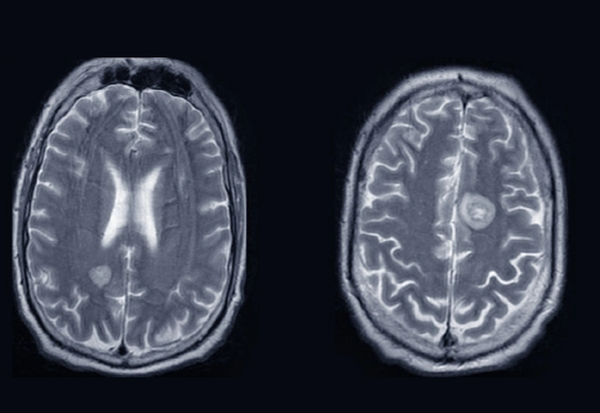

За разлика од претходните извештаи, овој пациент првично немал никакви забележливи тумори во мозокот, иако некои се појавиле како што напредувала болеста.

Со оглед на времето, лекарите се сомневаат дека FAS на пациентот е резултат на ретко паранеопластично невролошко нарушување. Ова нарушување е предизвикaно кога ракот надвор од мозокот предизвикува имунолошки одговор кој може да влијае врз нервниот систем оддалеку.

Фото: Broderick et al., BMJ Case Report, 2023